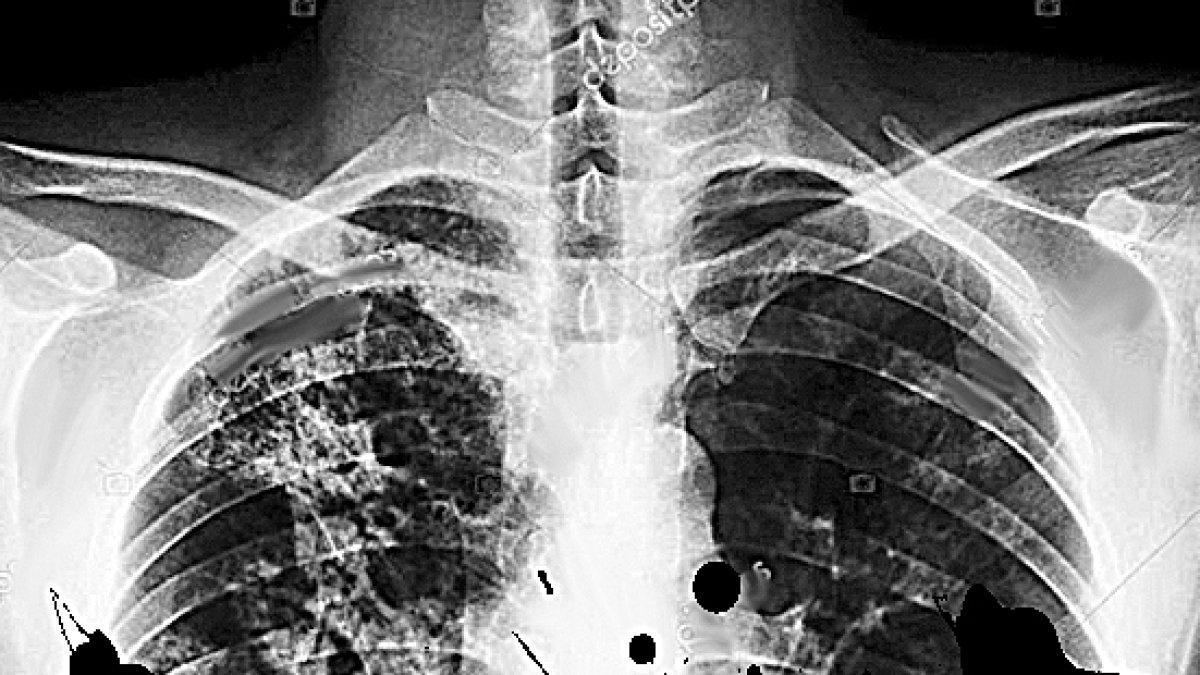

Tuberculosis: como ganarle la guerra

El mundo finalmente está despertando a la amenaza planteada por una de las enfermedades más subestimadas de nuestro tiempo. El mes pasado, la Asamblea General de las NN. UU. fue sede de la primera reunión de alto nivel en la historia sobre tuberculosis (TB), con el objetivo de explorar opciones para los esfuerzos de erradicación internacional. El camino para vencerla empieza en África; un cuarto de todas las muertes por TB a nivel mundial ocurren allí. En 2016, unas 417.000 personas sucumbieron a la enfermedad. Brotes recientes resistente a múltiples drogas y de TB extremadamente resistente a las drogas en Sudáfrica, Mozambique y Ghana podrían elevar más el total de muertes anuales. Estos bolsones de la bacteria, hoy completamente inmune al tratamiento antimicrobiano, implican que el desafío de la erradicación global sea todavía más desalentador. Parte del motivo de la persistencia de la TB es la vulnerabilidad de las poblaciones a las que infecta. Está entre los principales responsables de la muerte de personas VIH positivas y la causa de muerte de alrededor del 40 % por VIH, lo que plantea peligros para los pacientes que no lo tienen (inmunodeprimidos, niños pequeños y bebés). La erradicación también es difícil porque la TB es una bacteria sumamente contagiosa que se propaga por el aire. La gente que vive y trabaja en espacios cerrados -como mineros, presos, migrantes y refugiados- sufren las tasas más altas de infección. La prevalencia de la TB está estrechamente asociada a la pobreza y a la marginación social, y llegar a quienes están más en riesgo no es fácil. Las enfermedades infecciosas no tienen fronteras y en la medida que los países africanos profundicen sus vínculos comerciales y crezca la migración al interior de África, la amenaza de una pandemia regional aumentará. África debe comenzar a desarrollar una estrategia integrada de múltiples sectores para contener, controlar y erradicar los desafíos a la salud pública como la TB. Los gobiernos africanos podrían emular la estrategia de gestión del sector minero, un plan interinstitucional diseñado en 2014 por la Comunidad de Desarrollo de África Austral. Antes de acordar un marco específico requieren atención urgente los planificadores de atención médica y que los especialistas en enfermedades de África fijen objetivos de contención a nivel local, regional y por país. Para terminar completamente con la TB, África necesitará nuevos compromisos financieros sostenidos de parte del sector público y privado, y diseñar estrategias de control de la enfermedad para sustentar las prioridades económicas y de atención médica de las Comunidades Económicas Regionales. Los responsables africanos de las políticas deben desarrollar sistemas para prevención, diagnóstico y atención que ayuden a los gobiernos a compartir la carga de la enfermedad y garantizar que los protocolos de tratamiento sean consistentes en las diferentes regiones. Existen algunas tendencias positivas en la lucha contra la TB. Tasas de infección globales cayendo y que la OMS y la Unión Africana estén empezando a generar hojas de ruta para la erradicación de la TB. Aun así, sustentar este progreso en África exigirá una coordinación regional significativa y mucho dinero. Incluso aquellos africanos lo suficientemente afortunados como para obtener el tratamiento -seis a ocho meses de antibióticos fuertes- todavía enfrenta una posibilidad del 20 % de recaída. El objetivo de erradicar la TB está a nuestro alcance, pero debemos recordar que en África la batalla está lejos de haber acabado.